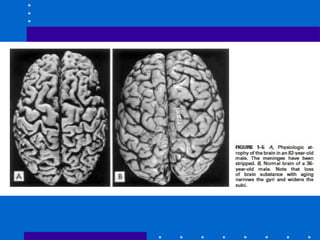

• 3.- Atrofia:

• disminucion del tamano de la celula por

perdida de sustancia celular.

• Envejecimiento.

• Presion.